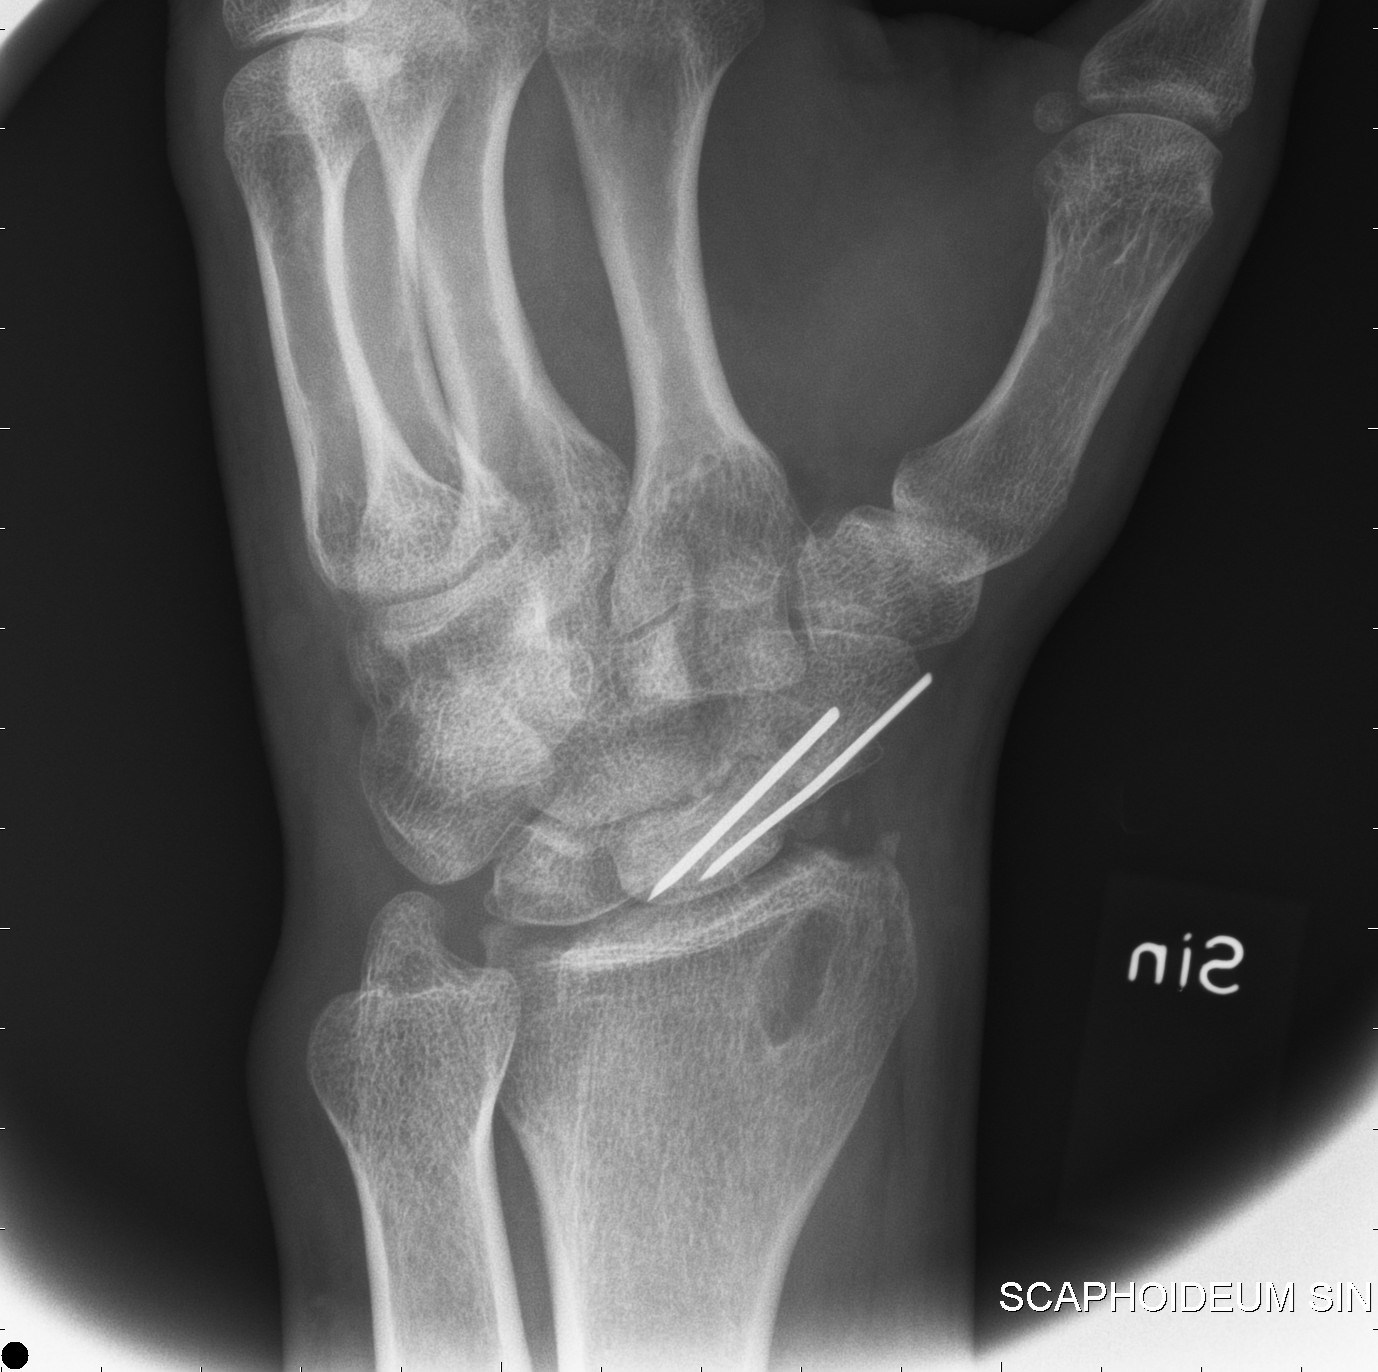

Bennetfraktur

Bennetfraktur är en intraartikulär luxationsfraktur genom basen av metacarpale I. Metacarpalbasen tenderar att luxera genom APL senans dragning i radiell-proxmal riktning. Frakturen behöver därför i princip alltid reponeras och immobiliseras internt med stift. Kan se väldig beskedlig ut på primära bilder men dislocerar succesivt genom senans dragning – klassificeras därför som ”lurig”.

Mekanism vid Bennetfraktur

Bennetfraktur där det ulnara fragmentet i basen på metkarpalen hålls kvar med hjälp av ligament i karpus. På grund av drag i abductor pollicis longus (APL) uppstår nästan alltid en diastas i frakturen. Diastasen i ledytan ger sekundärt artros. Dessa frakturer kräver således exakt fixation – vanligen i form av stift eller skruv.